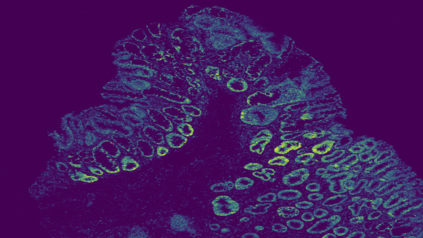

The usage of chemical imaging technologies is becoming a routine accompaniment to traditional methods in pathology. Significant technological advances have developed these next generation techniques to provide rich, spatially resolved, multidimensional chemical images. The rise of digital pathology has significantly enhanced the synergy of these imaging modalities with optical microscopy and immunohistochemistry, enhancing our understanding of the biological mechanisms and progression of diseases. Techniques such as imaging mass cytometry provide labelled multidimensional (multiplex) images of specific components used in conjunction with digital pathology techniques. These powerful techniques generate a wealth of high dimensional data that create significant challenges in data analysis. Unsupervised methods such as clustering are an attractive way to analyse these data, however, they require the selection of parameters such as the number of clusters. Here we propose a methodology to estimate the number of clusters in an automatic data-driven manner using a deep sparse autoencoder to embed the data into a lower dimensional space. We compute the density of regions in the embedded space, the majority of which are empty, enabling the high density regions to be detected as outliers and provide an estimate for the number of clusters. This framework provides a fully unsupervised and data-driven method to analyse multidimensional data. In this work we demonstrate our method using 45 multiplex imaging mass cytometry datasets. Moreover, our model is trained using only one of the datasets and the learned embedding is applied to the remaining 44 images providing an efficient process for data analysis. Finally, we demonstrate the high computational efficiency of our method which is two orders of magnitude faster than estimating via computing the sum squared distances as a function of cluster number.